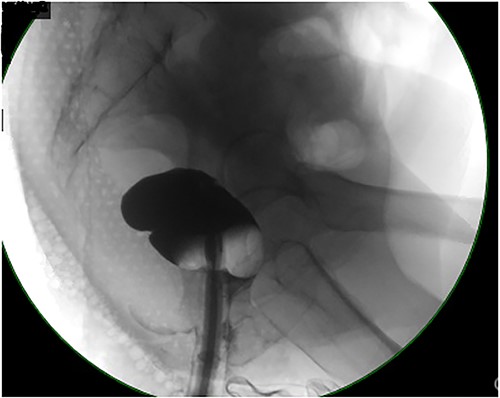

Computed tomography (CT) abdomen and pelvis revealed large bowel obstruction and high-grade stricture, with a miniscule residual lumen (Fig. 1). A nasogastric tube was placed for decompression, with significant output. CT chest showed no evidence of widespread disease. Gastrografin enema was performed to evaluate the obstructive lesion, and to rule out any synchronous proximal lesions, as shown in Fig. 2, no contrast passed beyond the rectal stricture.

Contrast enema showing no retrograde filling due to low rectal stricture.